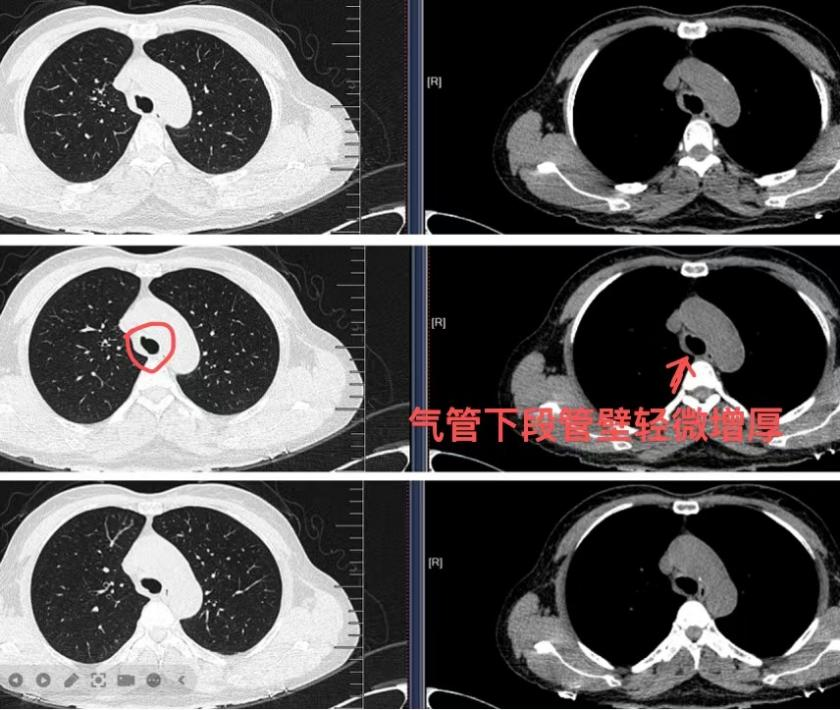

患者秦女士,中年女性,因持续干咳半年余,辗转多家医院就诊,均被诊断为“咳嗽变异性哮喘”,但抗哮喘治疗始终未见明显效果。患者阵发性咳嗽昼夜难眠,给生活和工作带来很大困扰。经朋友介绍至南溪山医院呼吸与危重症医学科二病区(简称呼吸二病区),屈东明博士详细追问病史并重新评估病情,凭借丰富的临床经验,敏锐察觉到病因的复杂性,通过肺部CT检查发现患者气管下段稍隆起,随即建议行电子支气管镜检查。检查中发现气管下段及右主支气管内大量干酪样坏死物,经肺泡灌洗液检测(TB-DNA阳性、抗酸染色阳性+2),最终确诊为“支气管结核”。目前患者已转入结核专科接受规范治疗,病情逐步好转。

呼吸二病区科主任屈东明博士介绍,支气管结核临床表现多样,易与慢性咳嗽、哮喘、肺部肿瘤等疾病混淆,误诊、漏诊率较高。本例患者病灶位于大气道,CT仅显示轻微隆起,若非支气管镜直视观察,极易延误诊治。“长期不明原因咳嗽需警惕感染、肿瘤、结核等非典型病因,及时完善影像及内镜检查至关重要。”

此次病例的快速确诊得益于该院呼吸与危重症医学科、医学影像科及检验科的高效联动。从CT影像的细致判读到支气管镜的精准取材,再到实验室的快速检测,环环相扣的协作模式为患者赢得了治疗时机。